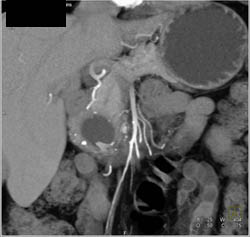

Pancreatic Transplant